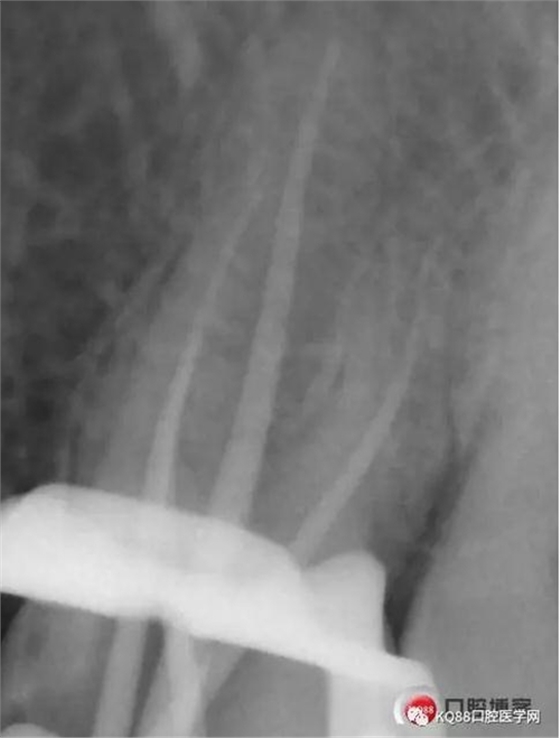

此次明顯可以看見(jiàn)根尖分開了兩個(gè)根尖孔,根管治療永遠(yuǎn)就只是那一點(diǎn),如果都只是隨便做一下,我相信,沒(méi)有復(fù)雜的牙齒,根管治療都會(huì)很簡(jiǎn)單,態(tài)度決定一切,我不敢說(shuō)我做的會(huì)很好,但是我會(huì)靜下心來(lái),慢慢操作,這樣才能做得對(duì)的起自己和患者。于是根充完成,再次拍攝。

Y形態(tài)變形成了,根間支也明顯出現(xiàn),充填嚴(yán)密,雖然根管治療的成功率不是一百,但是我們盡可能把那一點(diǎn)做到位,往往結(jié)果可能會(huì)很驚人,如果我在第一次就充填了,可能也不會(huì)有什么錯(cuò)誤,但是態(tài)度就已經(jīng)輸了,我們基層做根管不會(huì)像武大等那么規(guī)范,但是也希望可以向其靠攏,一個(gè)好的根管,上面才能有美的修復(fù)。